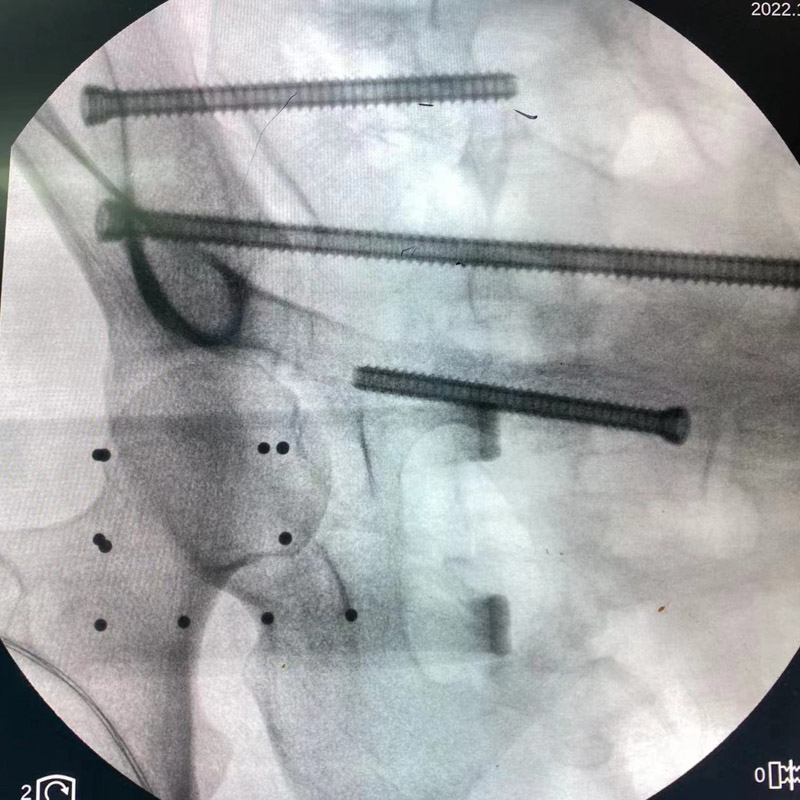

術中,創傷骨科團隊將示蹤器安裝在患者手術處,與移動C型臂X光機相配合,手術團隊根據生成圖像模擬置釘,通過獨有算法計算出入釘點及釘道,按照術中規劃,施術者借助導向套筒,為患者精準的植入三枚螺釘,手術切口僅三個1厘米小洞,術中出血不到10毫升。